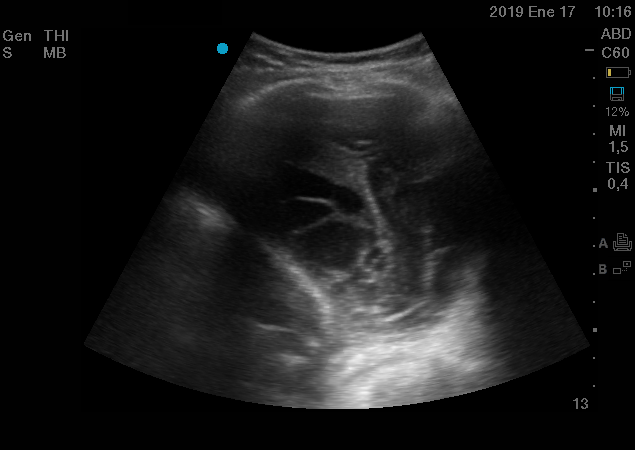

Curso de ecografía crítica en todas sus modalidades (ecocardiografía transtorácica y transesofágica, ecografía pulmonar, vascular, cerebral, FAST) dirigido a: médicos intensivistas, emergenciólogos, anestesiólogos, internistas, médicos de familia, neumólogos, cardiólogos y a todo aquel interesado por utilizar la ecografía como parte del examen físico del paciente crítico.

Para diagnosticar las diferentes patologías que pueden causar insuficiencia respiratoria aguda tales como neumotórax, neumonía, derrame pleural, síndrome alveolo intersticial, también evaluar las terapéuticas administradas y evolución de las mismas.

En nuestro afán por seguir el trabajo empezado hace ya varios años desde Europa (España) por impulsar la ecografía crítica para intensivistas, emergenciólogos, anestesistas, internistas, subespecialistas de obstetricia crítica, neumólogos y todo aquel médico interesado en aprender a utilizar la ecografía como parte de su examen físico, ahora desde Centroamérica (Panamá), hemos escrito el primer libro Latinoamericano-Europeo de ecografía crítica sub-especializado y dedicado exclusivamente al paciente con shock de cualquier etiología (obstructivo, distributivo, cardiogénico, hipovolémico) que involucra todas las modalidades ecográficas: ecocardiografía, ecografía pulmonar, vascular, abdominal, del sistema nervioso central/doppler transcraneal, etc) en el que participan muchos expertos en sus respectivas áreas tanto de Europa como de América y también algunos profesores del EDEC (Diploma Europeo de ecocardiografía / ESCIM- Sociedad Europea de Medicina intensiva).